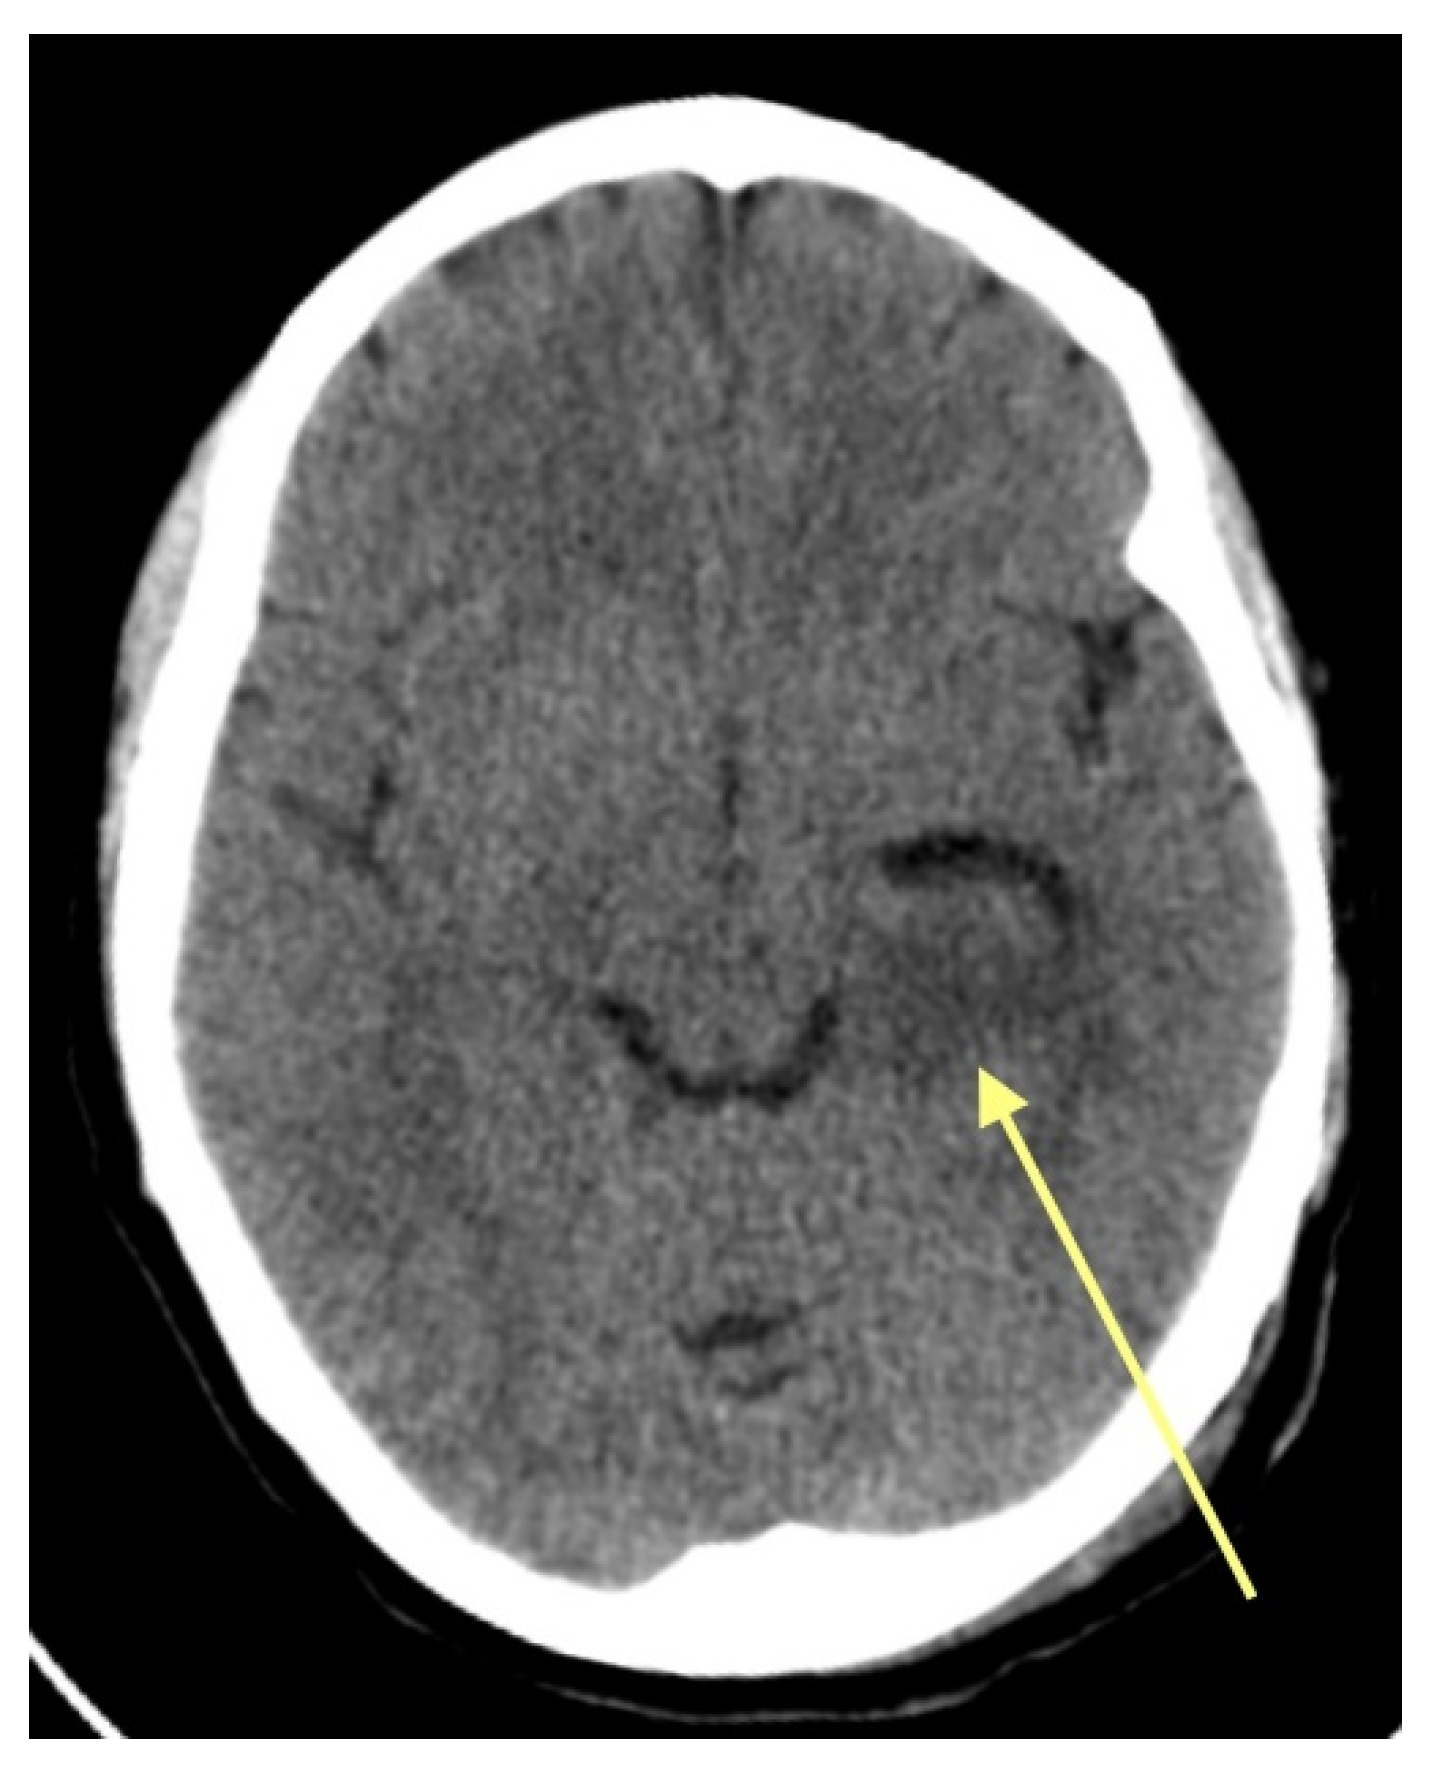

A 45-year-old female patient presented in the ED due to dysarthria, drooping of the mouth corner, and an epileptic episode that had occurred 4 h ago. She was a right-handed teacher with no significant medical history. She was evaluated by a neurologist who initially considered the possibility of an ischemic stroke in the differential diagnosis. A CT scan of the brain (Figure 1) was performed, which revealed a hypodense area in the left hippocampus. Subsequently, the patient was referred to the neurosurgical team. During the examination, the patient showed improvement in her dysarthria and did not present any other neurological deficits. There were no memory impairments and no focal neurological deficits. The patient was admitted for further investigation with an MRI of the brain. Signed informed consent was received from the patient and, since this is a retrospective reflection of the case, an Institutional Review Board Statement was not deemed necessary.

Figure 1.

Axial CT image. The yellow arrow shows the hypodense area at the area of the left hippocampus.